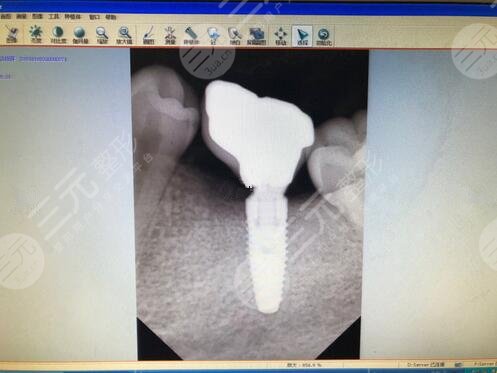

3.中山大学附属第一医院种植牙案例

在中山大学附属第一医院做种植牙手术的时候,医生先给我的牙齿进行了简单的清理,在确保没有炎症的情况下,才可以进行具体的种植手术操作,在做手术之前还需要将我之前的病牙拔除掉。我选择的是一个瑞士的种植体,大概花费了13,000元左右,手术下来大概花费了两三个月。